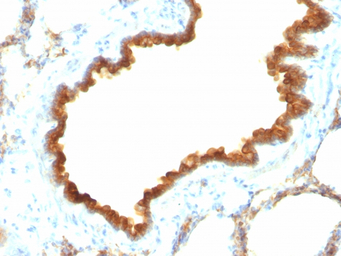

IHC-P analysis of rat lung tissue using GTX34651 Cytokeratin 19 antibody [KRT19/800].